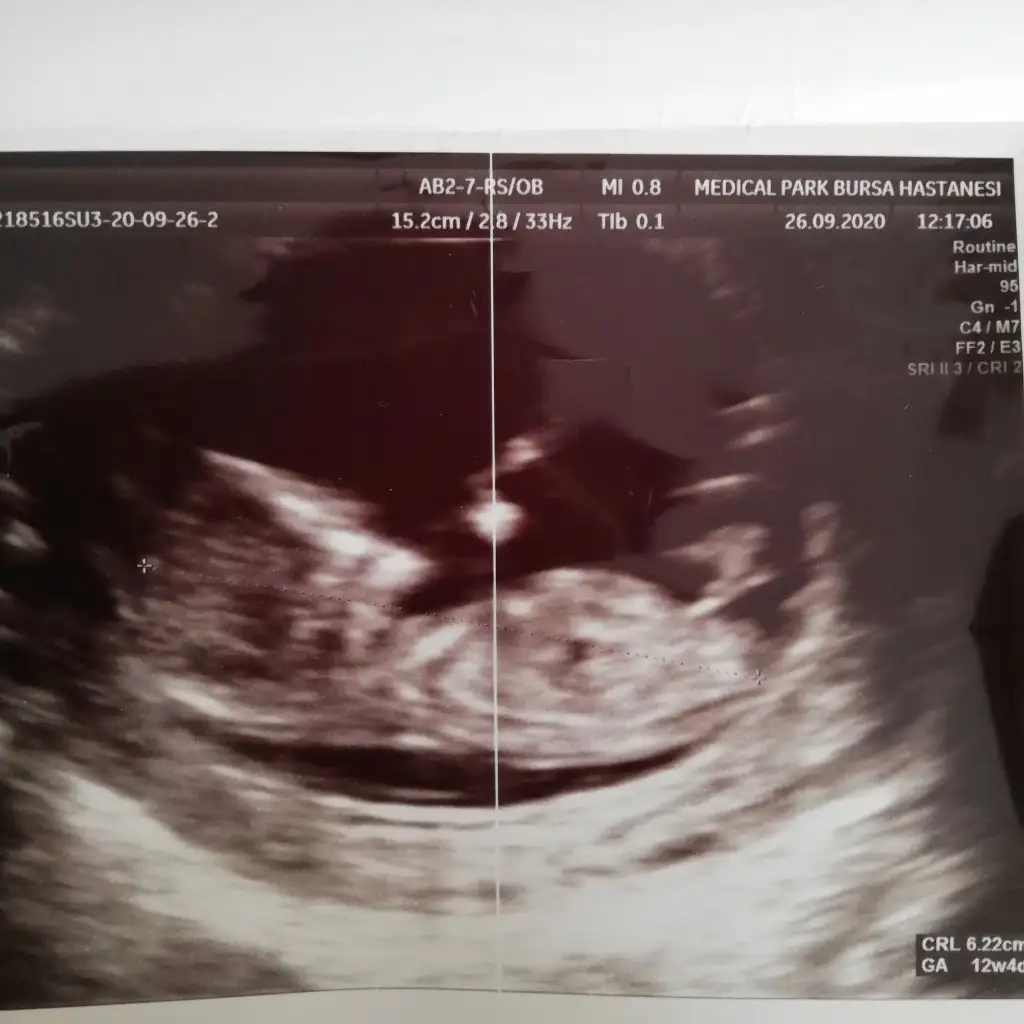

Canım Rukiye gönüllü dimi doktorum Bursa medikal park ta ben de gittim memnun kaldım senle konuşmuştuk cinsiyet tahmini yapmadımıÇektim

Evet canım rukiye hanım bende cok memnunum Aslında sordum tahmininiz varmı dye bakıcam dedi baktı yani çok erken sannki nokta gibi birşey var ama emin olamıyorum daha çok erken söylemek için dedi net görseydi söylerdi diye düşündüm çünkü bakıcam şimdi dedi göremeyince erken dedi bende ısrar etmedim daha bilemedim yaniCanım Rukiye gönüllü dimi doktorum Bursa medikal park ta ben de gittim memnun kaldım senle konuşmuştuk cinsiyet tahmini yapmadımı

Bana 15. Haftada erkek dedi baştan erkek dedi sonra bacaklarını kapattı dedi ayrıntılı ya çağırdı 15. HaftadaEvet canım rukiye hanım bende cok memnunum Aslında sordum tahmininiz varmı dye bakıcam dedi baktı yani çok erken sannki nokta gibi birşey var ama emin olamıyorum daha çok erken söylemek için dedi net görseydi söylerdi diye düşündüm çünkü bakıcam şimdi dedi göremeyince erken dedi bende ısrar etmedim daha bilemedim yani

Hayırlısı canım bende kızım olursa sevinirdim, tabi Rabbim hayırlısı neyse onu versin inşallah nokta gibi dedi sanırım pipi anlamında eminde değil ama ben erkeğe hazırlıyım kendimiBana 15. Haftada erkek dedi baştan erkek dedi sonra bacaklarını kapattı dedi ayrıntılı ya çağırdı 15. Haftada